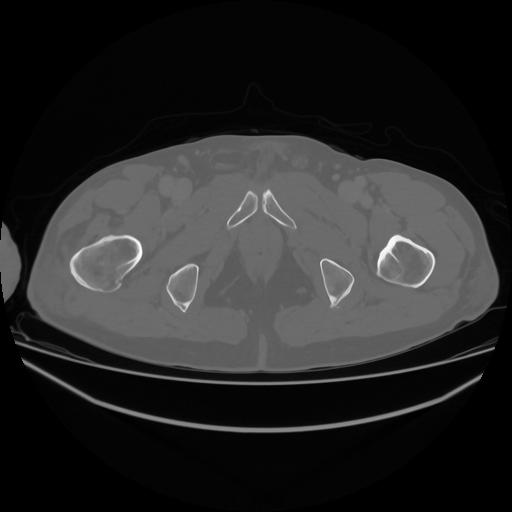

5 CUERPO,CE,Vol,1.0,CUERPO,,